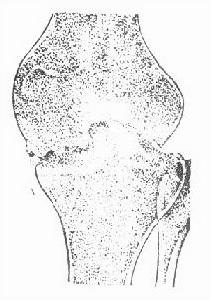

單純骨結核可見局部有溶骨性破壞,磨砂玻璃樣改變或死骨形成。

由單純滑膜轉變為全關節結核時,可見軟骨下骨板模糊或邊緣骨質破壞,晚期關節破壞嚴重,出現畸形或強直。